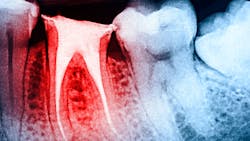

Pain after root canal therapy: Causes and considerations

Persistent tooth pain after root canal therapy can occur under several scenarios, and research suggests that between 4% and 6% of all teeth treated with root canals continue to be associated with lingering pain. Here are the three most common causes of pain that we see:

Complete removal of the diseased pulp is not achieved. Despite significant advancements in the delivery of root canal therapy to address tooth pain of deep somatic origin (the dental pulp), there are times when, as the result of the complexity of the root anatomy, challenges in providing complete anesthesia, managing patient comfort in the chair, and limited technical skill and experience of the provider, complete removal of the diseased pulp is not achieved.

As a result, pain continues, though the patient was advised that treatment was completed. In these scenarios, re-treatment of the tooth (often with the assistance of cone beam imaging and microscopic visualization if not used prior, or with a specialist) may be required to determine where the first treatment efforts fell short. Once addressed, these types of lingering pain problems mostly resolve.

Complete removal of the diseased pulp is achieved. At other times, technical success is fully achieved in removing the compromised dental pulp, but due to the chronicity of the pulpal compromise before removal or its origin (trauma/fractured tooth, etc.), nociception from an irritated or injured PDL is not turned off. The result is pain, which can be constant but often is most concerning while chewing. As a result, the patient totally avoids chewing on that side of the mouth.